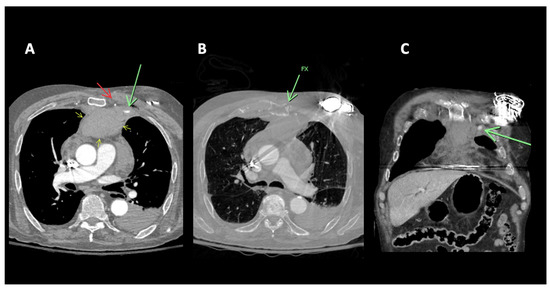

Pseudoaneurysms involving the internal mammary artery/internal thoracic artery (IMA/ITA) are rare occurrences, and the presentation and treatment approaches for such cases can be variable. Due to the potentially life-threatening risk of rupture, leading to conditions like hemothorax, it is important to have a comprehensive understanding of safe and effective diagnostic and therapeutic techniques. We present two cases of IMA/ITA artery pseudoaneurysms. A 91-year-old male presented to the emergency department following a motor vehicle accident. A CT scan of the chest revealed an anterior mediastinal hemorrhage with active extravasation. Percutaneous intervention revealed a pseudoaneurysm arising from a left IMA/ITA side branch. Coil embolization effectively treated the pseudoaneurysm. In the second case, a 79-year-old male presented with a sternal fracture after a ground-level fall, with parasternal hematoma and active bleeding (pseudoaneurysm) on Trauma Computerized Tomography of the chest with contrast. He underwent coil embolization, and subsequent post-procedure angiograms confirmed the effective occlusion of the left IMA/ITA, with no further visualization of the pseudoaneurysm. These two cases underscore the importance of tailored approaches in treating internal mammary artery pseudoaneurysms. Full article

Figure 1